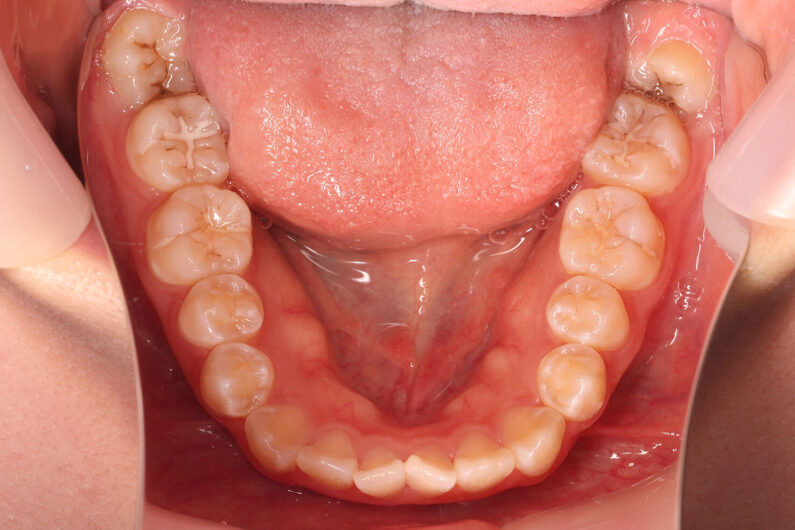

上顎前歯の強い叢生(がたつき)と、前歯部開咬状態でした。

マルチブラケット 動的治療期間 2年2か月 調整回数22回